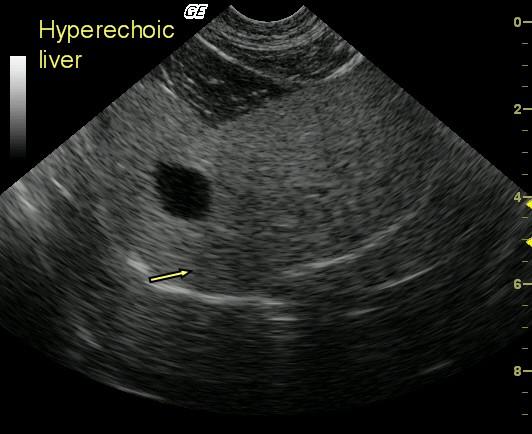

This 10 year old FS DLH cat presented for lethargy and anorexia. Physical examination revealed mild dehydration, poor coat quality, and mild jaundice. Blood analysis revealed moderately elevated SAP and moderately elevated total bilirubin.